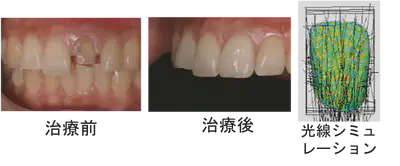

There have been ever-increasing demands for esthetics in the oral cavity after tooth restorations. Especially in the anterior, functional restoration is not enough; restored teeth should have similar color tones and light transmissions to natural teeth because the appearance of restored teeth when exposed to light varies greatly depending on the material used for the crown restoration device and the abutment structure.

Therefore, by analyzing the optical properties of various dental restoration materials and dental tissues via optical simulation, the behavior of light in natural teeth and dental restorations is visualized and analyzed for esthetic tooth restorations.